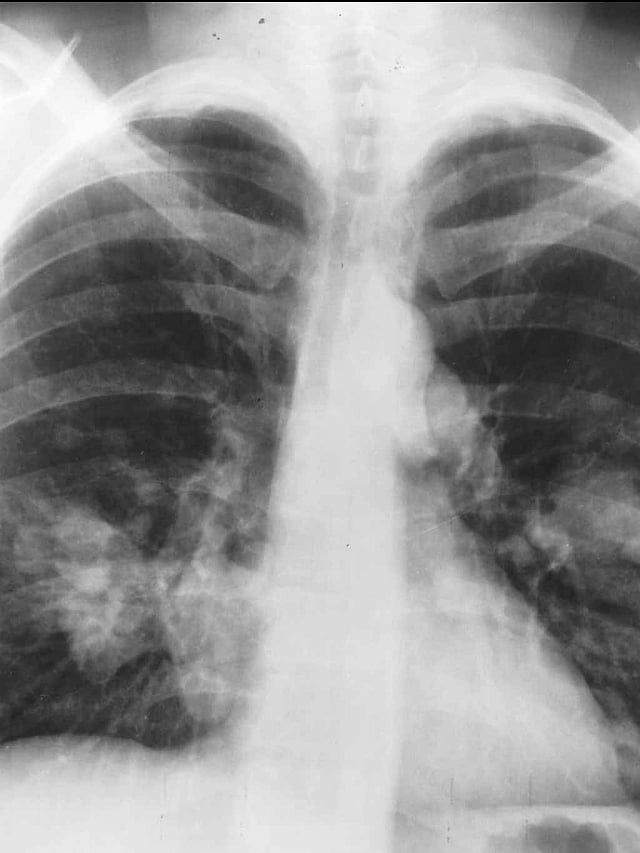

The research aims to predict long-term cardiac side effects from radiation therapy in lung cancer patients using machine learning.

Machine learning algorithms analyze standard lung-cancer scans to identify patients at risk of heart damage later in life.

The study represents the first application of functional radiomics to predict cardiac toxicity from medical images.